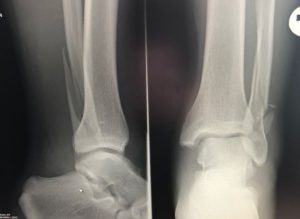

Консолидированный перелом на рентгене

Для определения наличия перелома и его характера необходимо провести диагностические исследования, первым из которых является рентгеноскопия. Рентгеновский снимок выполняют в двух проекциях: боковой и передне-задней.